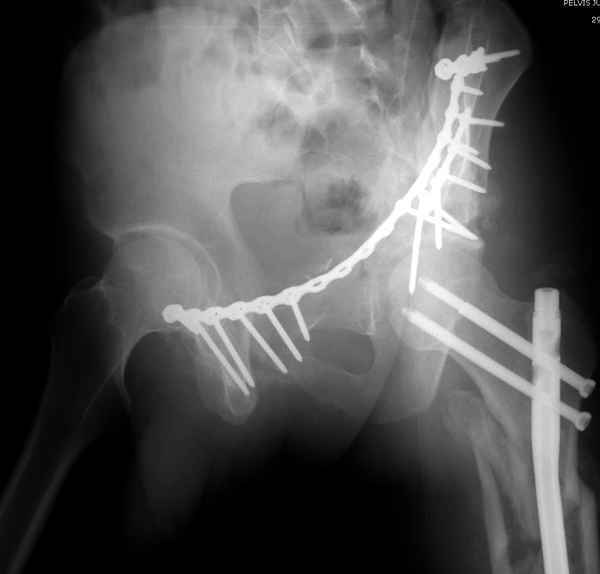

А что Ввам не понятно? И что Вам дадут нового в понимании паттерна данного повреждения "стандартные проекции"? Согласен! Есть детали, которые требуют осмотра пациента, но это детали. А тактика, как уже и говорилось: Реконструкция, потом эндопротезирование. Доступ... Впрочем, нагляднее посмотреть презентацию (прикрепленный файл). В представленном случае все делалось одномоментно - реконструкция и эндопротезирование. Доступы сочетались (задний и подвздошно-паховый). В данном же случае желательно выполнить в 2 этапа.

|

понимание Классификации Летурнеля позволило бы вам скорее всего выполнить реконструкцию под эндопротез из одного стандартного доступа в одну сессию, а не из двух с непонятным отпиливанием крыльев. Два доступа имели бы смысл, если бы планировалась полная реконструкция сустава в расчете на его функционирование его какое-то время. Представленный вами случай задает больше вопросов, чем ответов. Стоило затевать такую реконструкцию, чтоб установить обычную цементную чашку. Зачем 2 этапа для первичного эндопротезирования?

Из какого одного "стандартного" доступа вы собираетесь выполнить реконструкцию спустя 3 месяца? Из расширенного подвздошно-бедренного или У-образного с flip остеотомией большого вертела. В обеих случаях, скорее всего, разрез будет в проекции послеоперационного рубца. А мы даже пациента не видели. А задние отделы?!!! Надо фиксировать или нет? А если надо, то как, каким доступом? У "непонятного" отпиливания крыла - есть вполне понятные причины и обоснование. Это не ново! Или перкутанно фиксировать КПС? (спустя 3 месяца)!

А почему в 2 этапа? Исключительно для установки press-fit, а не обычную цементную чашку в реконструированную первым этапом и сросшуюся вертлужную впадину.

Здесь несколько вариантов двухколонных свежих переломов, которые были оперированы из одного-заднего, а также из двух: переднего и заднего доступов.